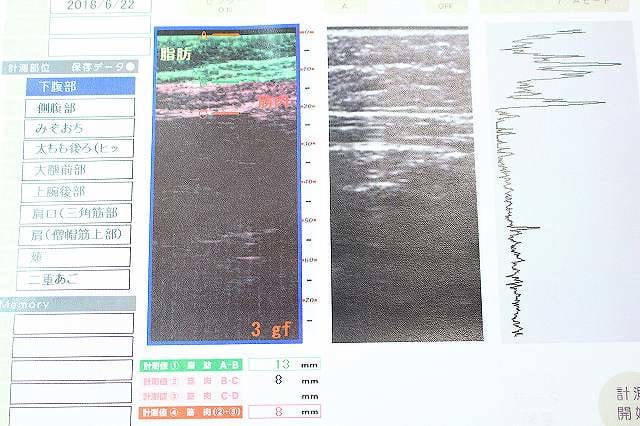

脂肪測定システムとは妊娠時のエコーと同じような原理で、超音波で皮下最大7cmまで見ることができるシステム。

小さな機械を気になる部分にピッと当てるだけで部分的な脂肪・筋肉の厚さ、質などを確認することができます。これによって、人それぞれに見合った痩身エステコースの提案してくれるそうです。100人100通りのコースが実現します!

私の脂肪測定システムの結果がこちら

こちらは下腹部の様子。脂肪の厚さは13mmと一般女性の標準値でした。よかった~(泣)

しかし、筋肉の厚さは8mmと、標準より1mm薄い結果に…。

シーズ・ラボのスタッフさん曰く、筋肉が薄いので腹筋がうまく使えてないとのこと。薄いとなかなか脂肪の燃焼に繋がらず痩せにくいとのことです。